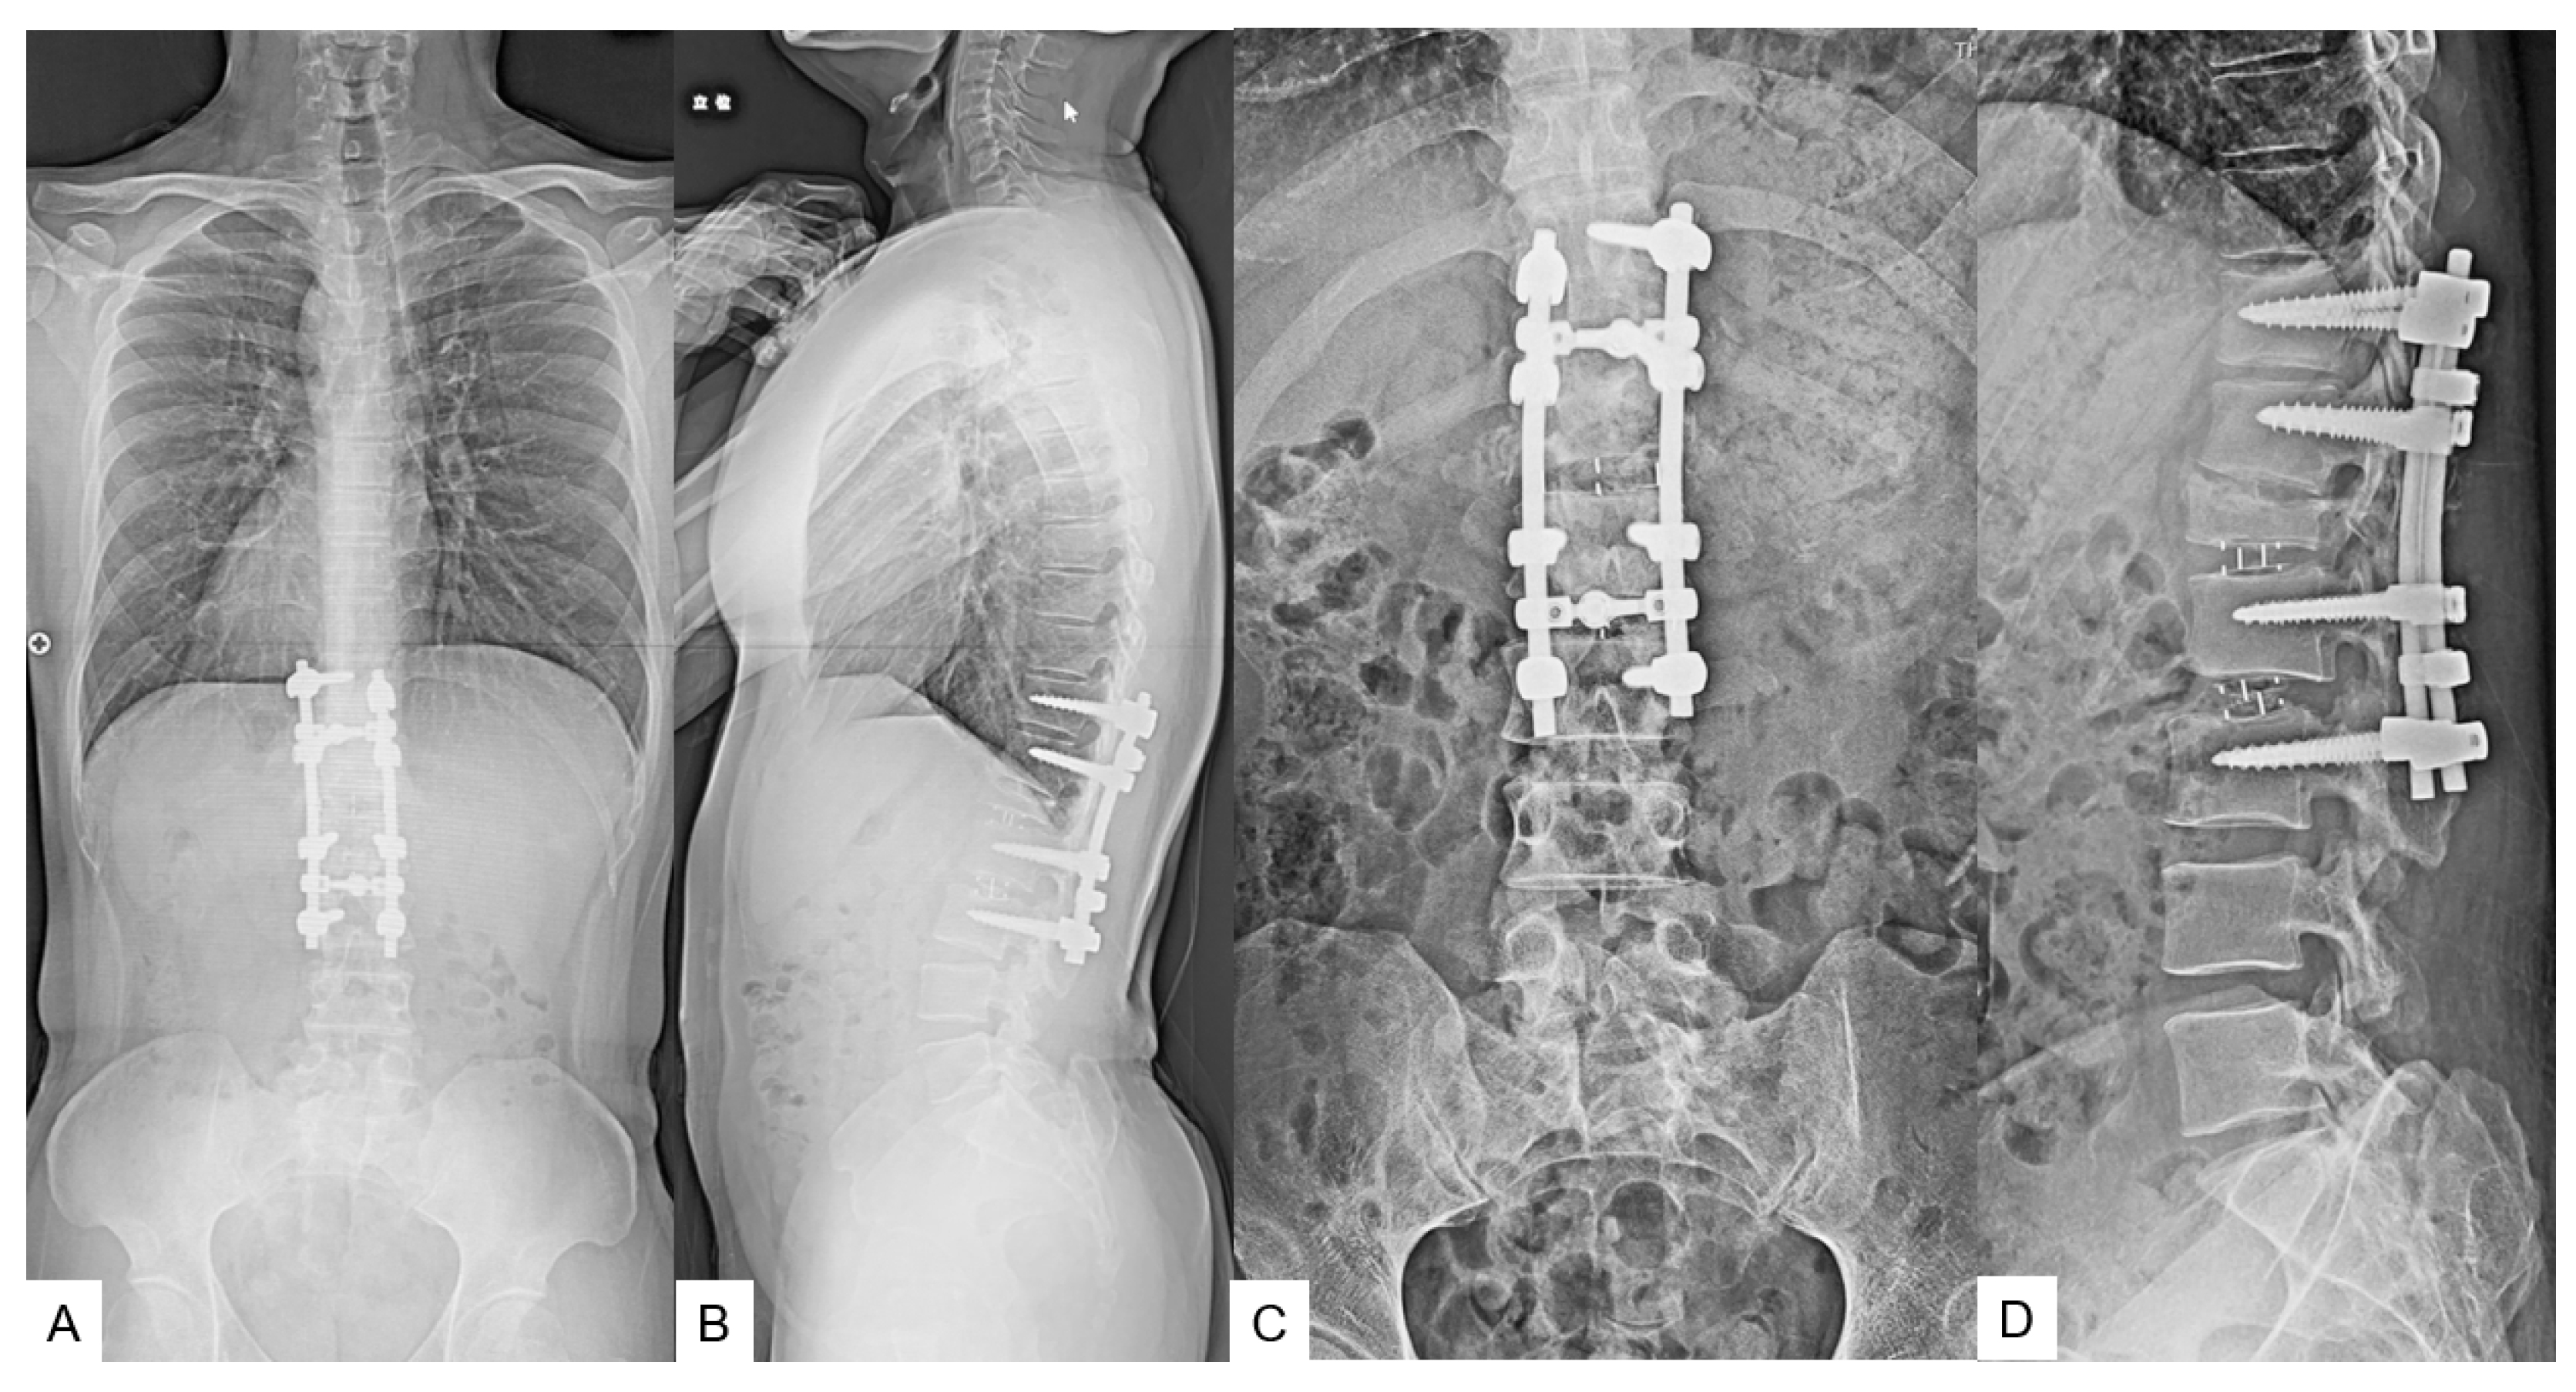

2.5. Postoperative Images

2.6. One Year Follow-Up